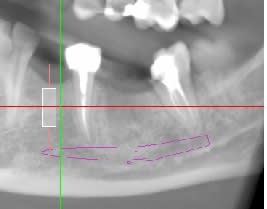

Faut il opter pour un implant de longueur 8x4.3 ou 10x4.3 (je pose du Nobel Replace CC), au vue des scanners ?

Je ne sais pas si un 8 mm suffit mais au vu du scanner (les implants dessinés font les vrais longueurs, cad 8.6 et 10.6mm.) je trouve que le trou mentonnier est proche...sachant que les forets sont encore plus longs que l'implant.

--- Pour la 36 :

Malgré la temporisation de un an, je trouve que la densité osseuse semble anormal au niveau du site d'extraction.

Tu parle d’examen scanner, mais j’ai l’impression que c’est un examen cone beam ?

> Tu parle d’examen scanner, mais j’ai l’impression que c’est un examen cone beam

Oui c'est bien un cone beam.

Avec un cone beam tu n’a pas la densité osseuse exacte et selon la machine utilisé la vision du volume et de la qualité peut être fausse. Dans un premier temps tu peux modifier les réglages d’apparence en te basant sur le rendu d’opacité des racines, ton ressenti sur la zone à implanté pourrai être différent. Seulement au moment de la clinique tu aura la réponse.